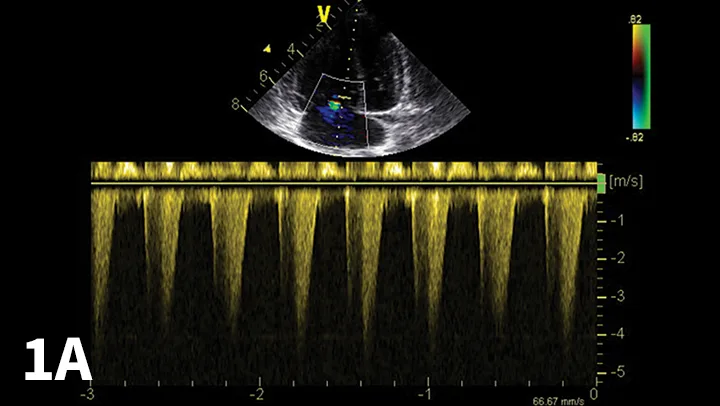

From the clinicians standpoint, echocardiography should be considered the most useful method to document PHTN (Figure 1).

Echocardiographic Doppler study documenting high tricuspid regurgitant velocity consistent with pulmonary hypertension. The modified Bernoulli equation [change in pressure = 4 (regurgitant velocity)2] may be used to estimate the systolic PAP. In the example shown, the tricuspid regurgitant velocity is 4.1 m/sec; thus, estimated PAP is 67 mm Hg.